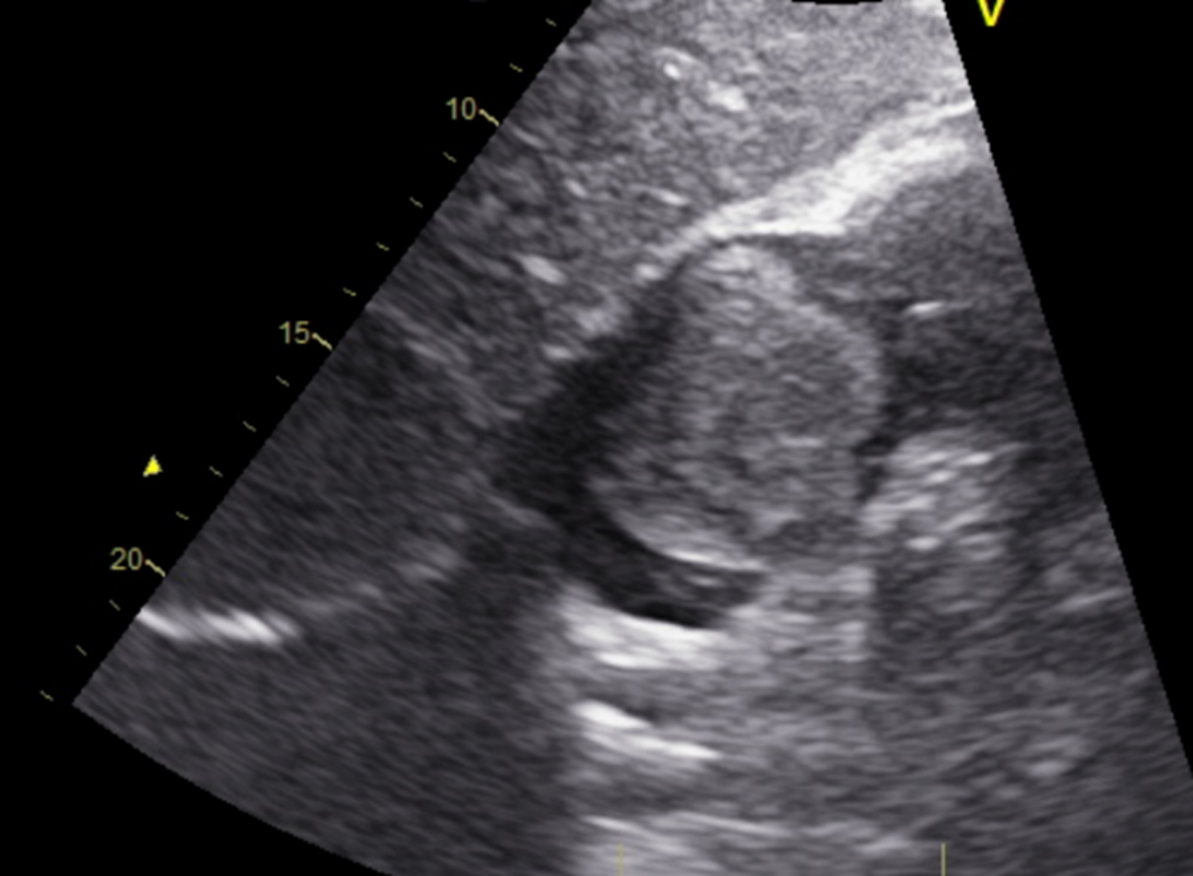

Posterior Chordae Rupture of the Tricuspid Valve due to Myocardial Infarction: A Rare Entity Among Tricuspid Valve Pathologies

Endri Balla, Okay Karslıoğlu, Zoukou Marie France Dominique Seri, Denizhan Akpınar, Ecem Tuğba Yamaç, Elshad Mansımzada, Hakkı Tankut Akay, Elvin Kesimci, Atila Sezgin

bjcr64